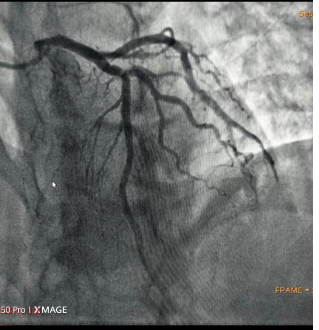

血管疏通后的心肌造影,可见血管清晰许多。

9月19日,47岁的市民刘先生(化名)与朋友就餐后返回家中,随即出现胸痛、胸闷、汗出,朋友将他送到市中医院急诊科,被初步诊断为急性广泛前壁心肌梗死。此时,刘先生已丧失意识,心室出现颤动。医生立即启动绿色通道,为他进行心肺复苏、心脏电除颤,并为其介入治疗,打通了他闭塞的冠状动脉血管,才使他转危为安。